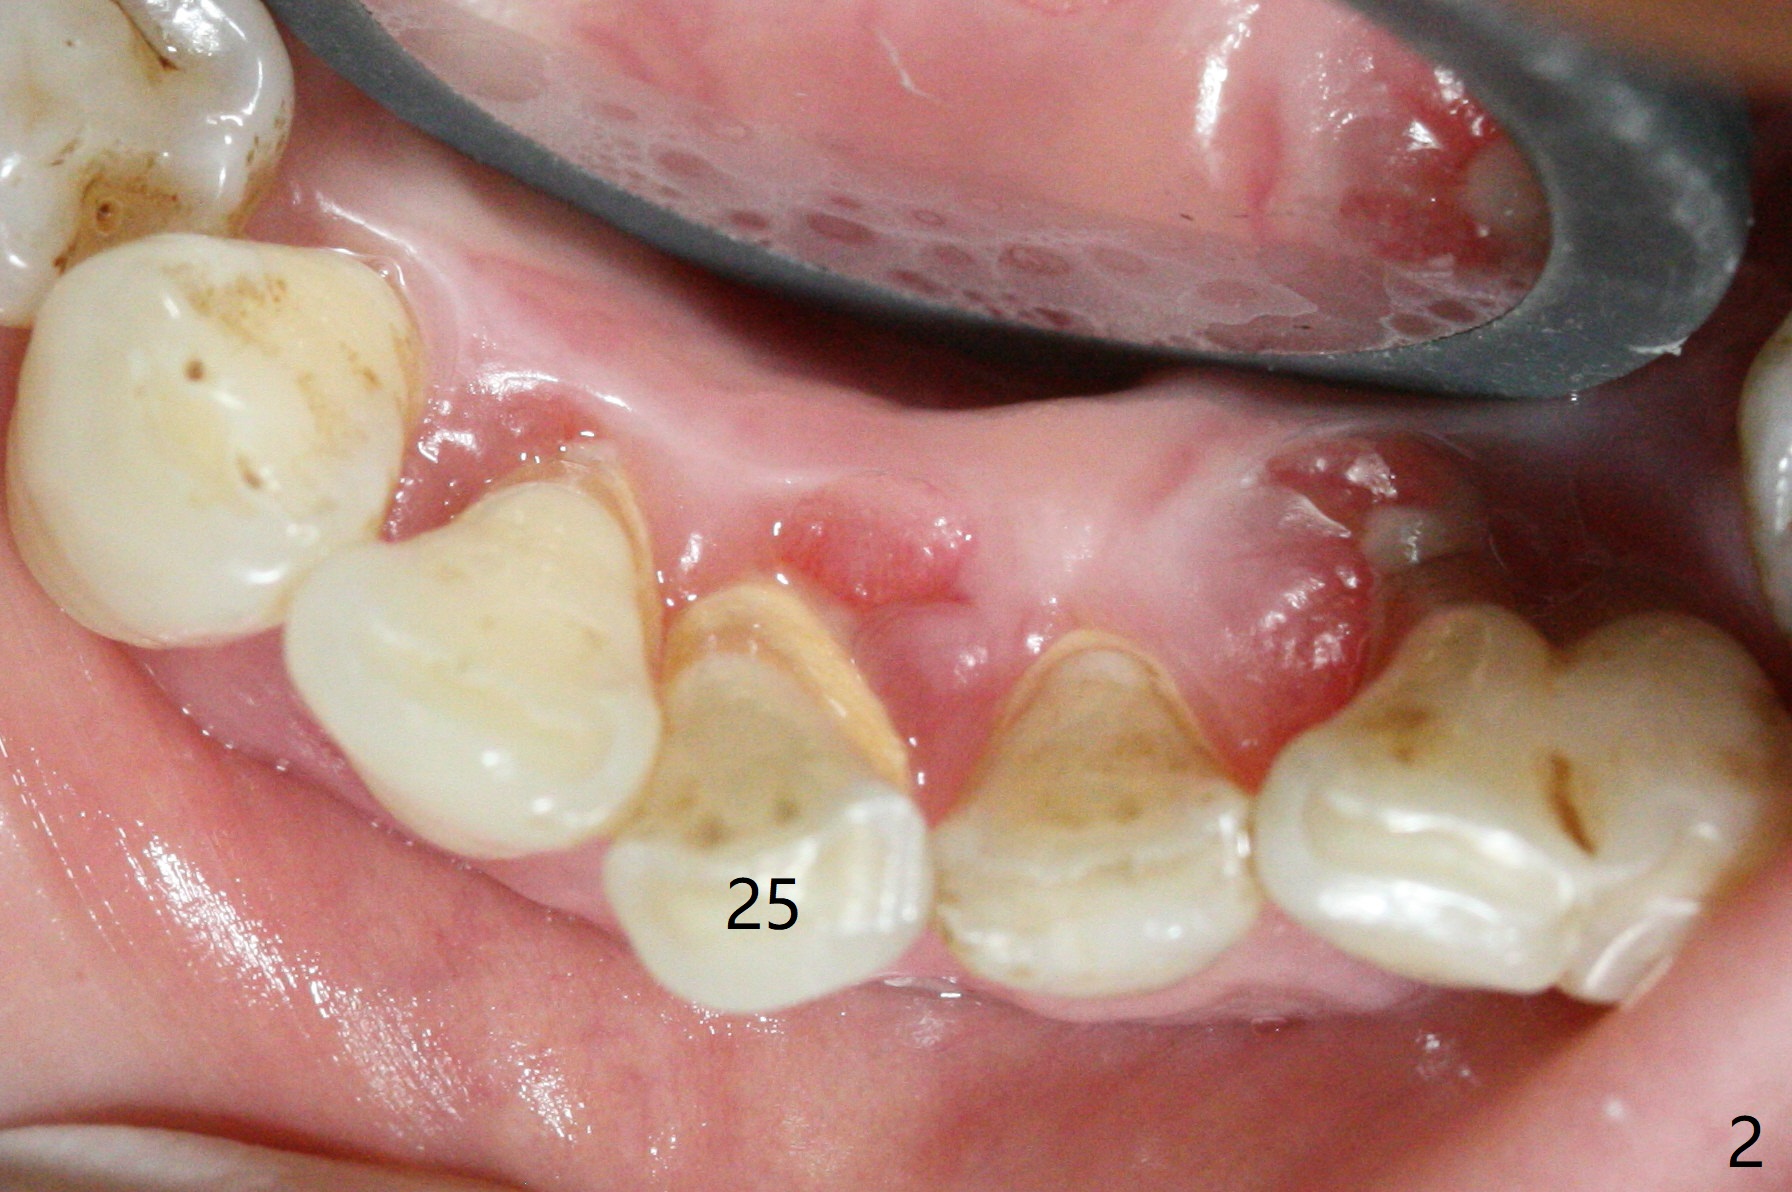

There is gingival inflammation at #25 buccally (Fig.1) and lingually (Fig.2). The bone loss is severe (Fig.3). Soft and hard tissue heights are 5 mm (cuff will be 4 mm) and 10 mm (implant will be 12 mm with 2 mm outside the native bone, Fig.4). The apex of the affected tooth appears deviated distal (Fig.5 *). The initial osteotomy happens to follow the long axis of the socket (Fig.6); to establish a correct trajectory, a new osteotomy should be made at the site labeled as a red line. In fact it is executed as planned (Fig.7). Because of the narrow flat ridge buccolingually, a 2.5x12(4) mm 1-piece implant is placed with >40 Ncm (Fig.8). With deeper placement of the implant, Vanilla graft is placed in 2 steps (Fig.9,10). The patient will return 2.5 months for extraction and implant of the fused teeth #22 and 23. No implant threads are exposed 10 months postop (Fig.11). CT taken 11 months postop shows that the 2.5 mm implant is in the middle of the bone (Fig.12) or 2 years post cementation (Fig.13).